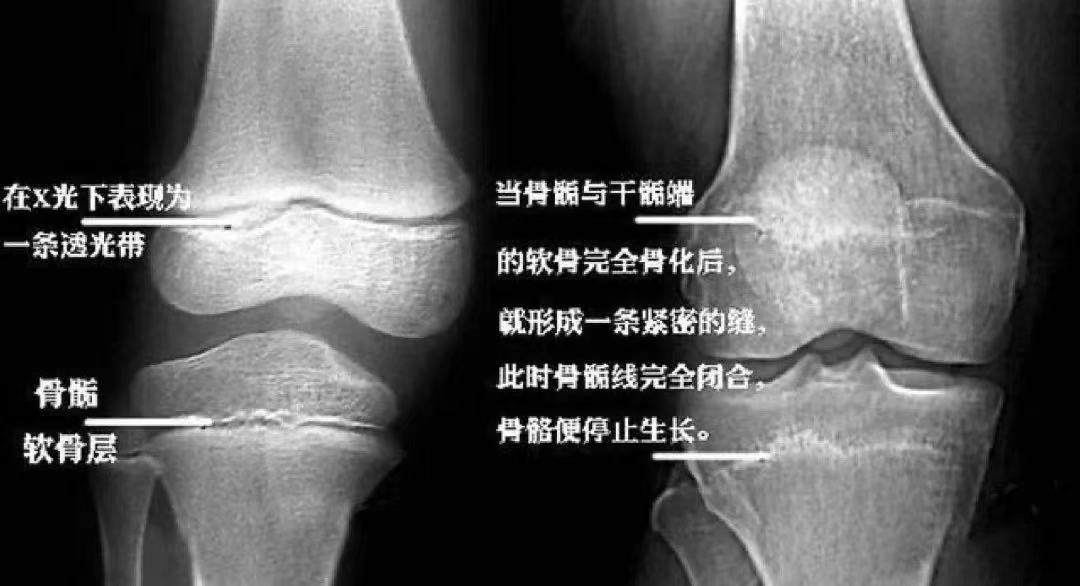

▲左图为4.7岁孩子的生长板,清晰可见

右图为17岁男孩,骨干骺端完全闭合,生长板消失

▲膝关节X光片